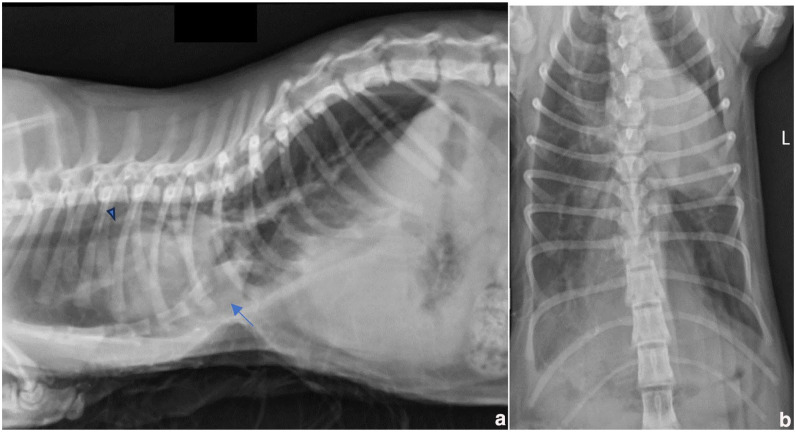

Case summary: A 4-month-old Maine Coon kitten was presented for the surgical correction of pectus excavatum (PE). Originally presenting with progressive respiratory distress, the cat underwent video-assisted thoracoscopic surgery (VATS) for stabilisation using a locking compression plate. Postoperative complications included two separate episodes of infection, which ultimately resolved after implant removal. The cat showed gradual improvement and exhibited no clinical signs related to PE at the 12-month follow-up.

Relevance and novel information: The VATS approach may provide a useful technique to help reduce intraoperative risk during PE correction in cats.